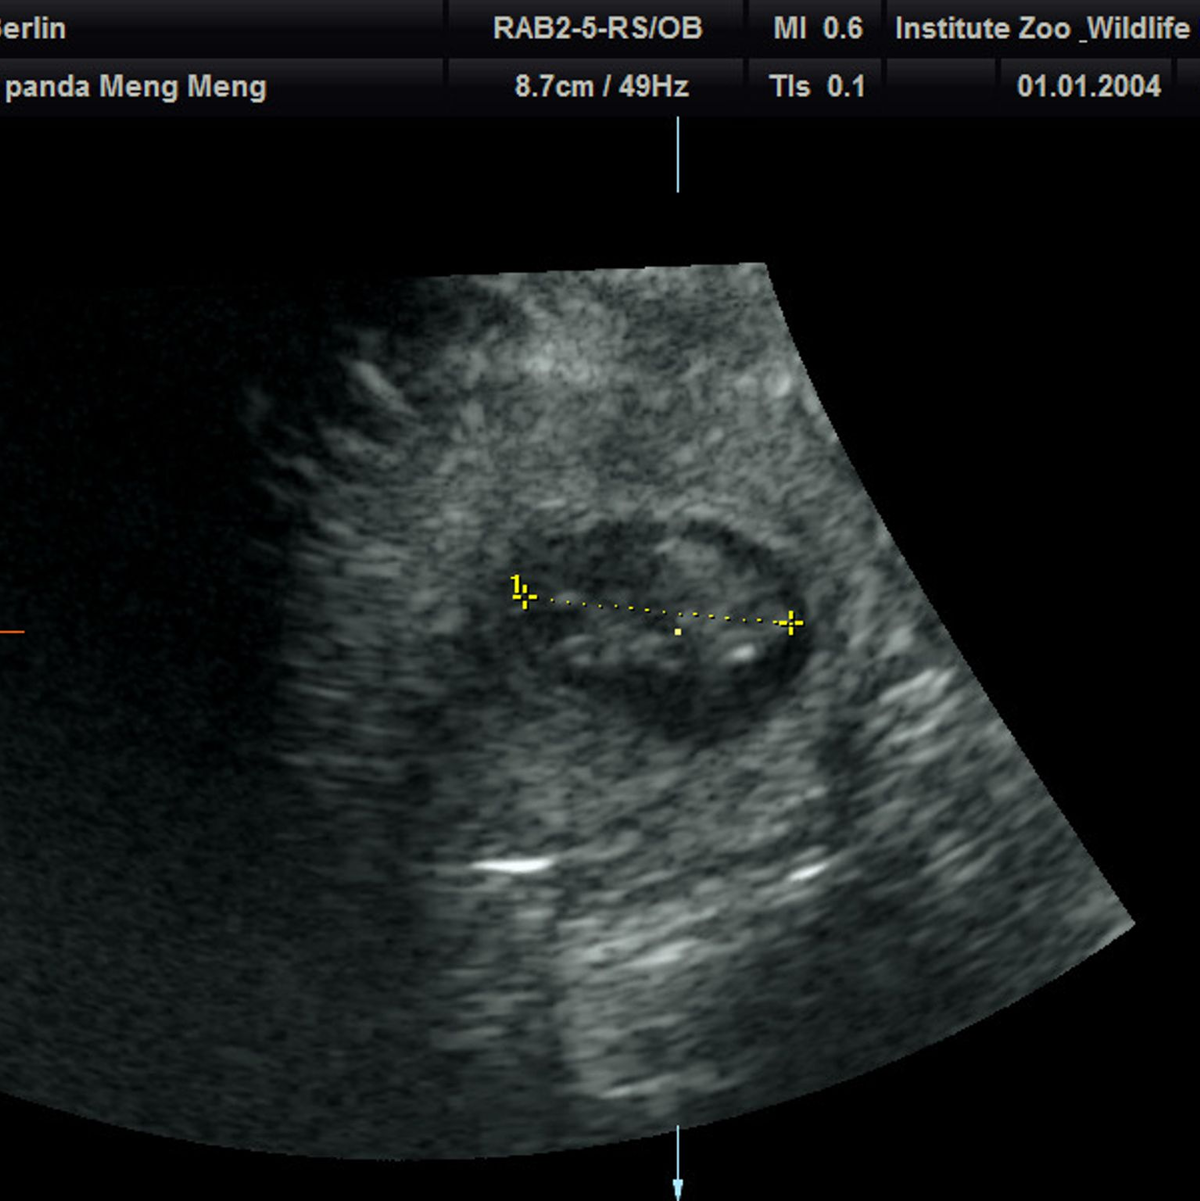

13.08.2024 - 08:49:13Nach fünf Jahren wird im Berliner Zoo wieder Panda-Nachwuchs erwartet. Das Pandaweibchen Meng Meng ist mit zwei Jungtieren trächtig, wie der Zoo am Dienstag mitteilte. «Nach Wochen gespannten Hoffens brach am Sonntagmorgen im Panda Garden des Zoo Berlin ein kleiner Jubel aus. Erst war ein Herzschlag, kurz darauf sogar ein zweiter auf dem Ultraschallgerät zu erkennen.» Die Pandababys seien etwa 2,5 Zentimeter groß und müssten bis zur Geburt jetzt noch ordentlich wachsen.

Kühles Ultraschall-Gel auf Panda-Bauch

Bei Ultraschall-Untersuchungen auf eine mögliche Schwangerschaft habe sich das Pandaweibchen zuletzt nicht besonders kooperativ gezeigt. Am Sonntag sei es aber gut gelaufen. «Trotz sichtlichen Bauchkneifens ließ sich Meng Meng überzeugen, in den aufrechten Stand zu kommen und das kühle Ultraschall-Gel sowie die Untersuchung mit der Ultraschall-Sonde zu akzeptieren», teilte Thomas Hildebrandt, Leiter der Abteilung für Reproduktionsmanagement am Leibniz-Institut für Zoo- und Wildtierforschung, mit. Die Untersuchung im Stehen habe schließlich die freudige Nachricht gebracht, dass Meng Meng trächtig sei.

Die Freude im Team sei riesig gewesen, weil es schon einige erfolglose Ultraschallversuche gegeben habe, sagte die Zootierärztin Franziska Sutter, die ebenfalls an der Untersuchung beteiligt war. «Bei aller Begeisterung müssen wir uns darüber im Klaren sein, dass das ein sehr frühes Stadium der Trächtigkeit ist und eine sogenannte Resorption – also ein Absterben - des Embryos zu diesem Zeitpunkt noch möglich ist.»